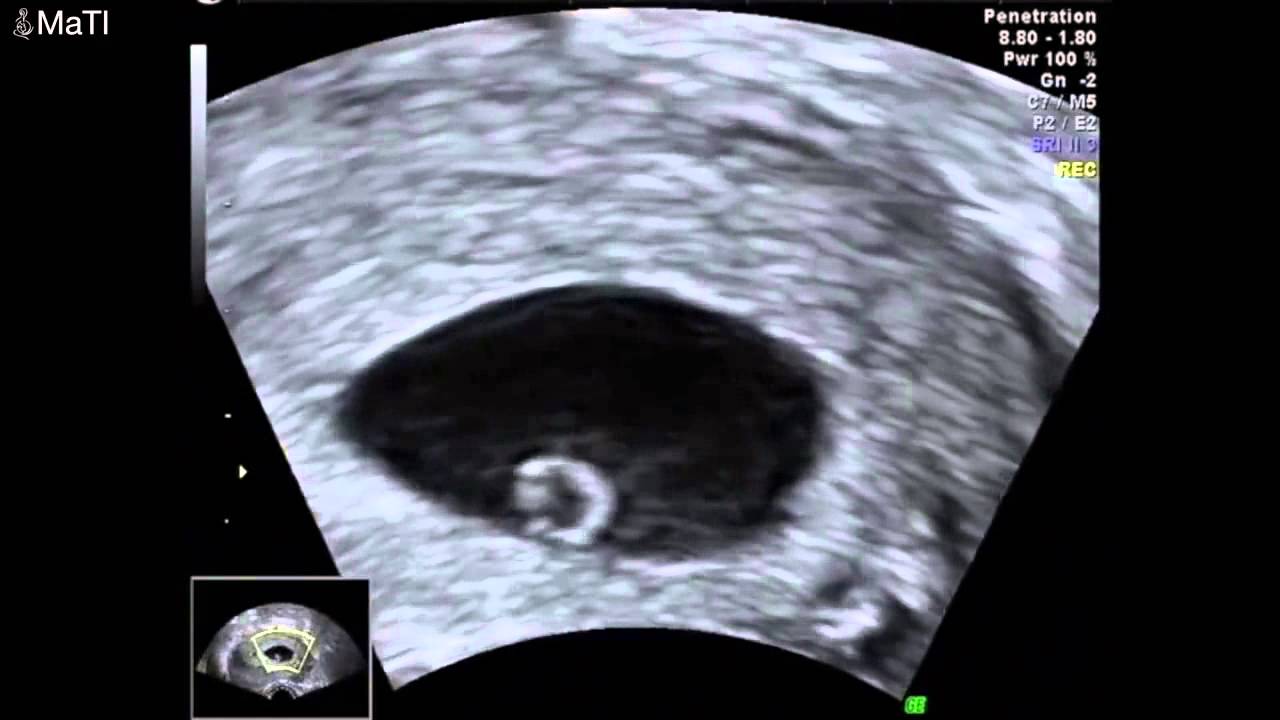

18 haftalık gebeliğin ultrason görüntüsü YouTube

16 HAFTALIK (3,5 AYLIK) KIZ BEBEK ULTRASON GÖRÜNTÜLERİ

21 HAFTALIK BEBEK ULTRASON GÖRÜNTÜLERİ YouTube